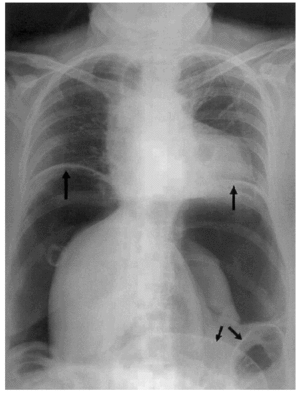

Se trata de una mujer de 56 años que presenta dolor abdominal cólico asociado a diarreas y heces mucosas valorada como gastroenteritis aguda. Por persistencia del cuadro, acude a urgencias 10 días después mostrando un abdomen distendido, no peritonítico. En la radiografía abdominal (fig. 1) se muestra neumoperitoneo masivo con desplazamiento diafragmático bilateral y dilatación colónica. La laparotomía exploradora mostró exudado purulento difuso, tumoración en sigma que se resecó realizándose colostomía terminal y perforación a nivel de colon ascendente que obligó a realizar cecostomía. El estudio anatomopatológico resultó compatible con adenocarcinoma mal diferenciado de sigma que infiltraba todas las capas de la pared cólica y la grasa pericólica junto con metástasis en 5 de los 9 ganglios linfáticos resecados, no hallándose evidencia de neoplasia en la perforación proximal.